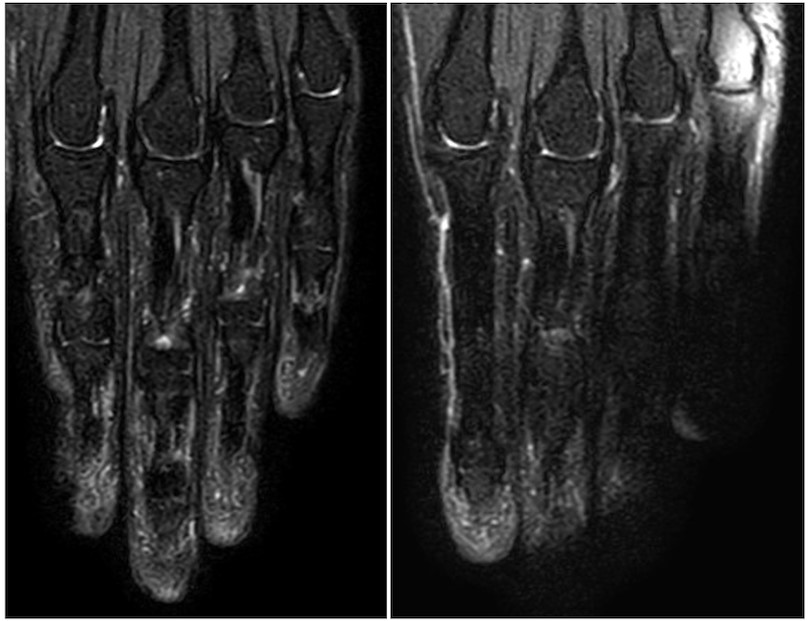

磁化率低減パッドとしてBB弾をストッキングなどに詰め、ポジショニング時に指または手の下/周囲に敷くことで、コイルと手指のあいだの空気層を減らし、B₁の不均一を軽減します(Fig.4)。

オフセンター配置でもBB弾を詰めたものを配置した方が、用いないものより明らかに脂肪信号の抑制不良や水信号の偽抑制が少ないことが確認できます(Fig.5)。また、BB弾ではなく米5)やガラスビーズ6)、小麦粉7)などを使った報告もあります。